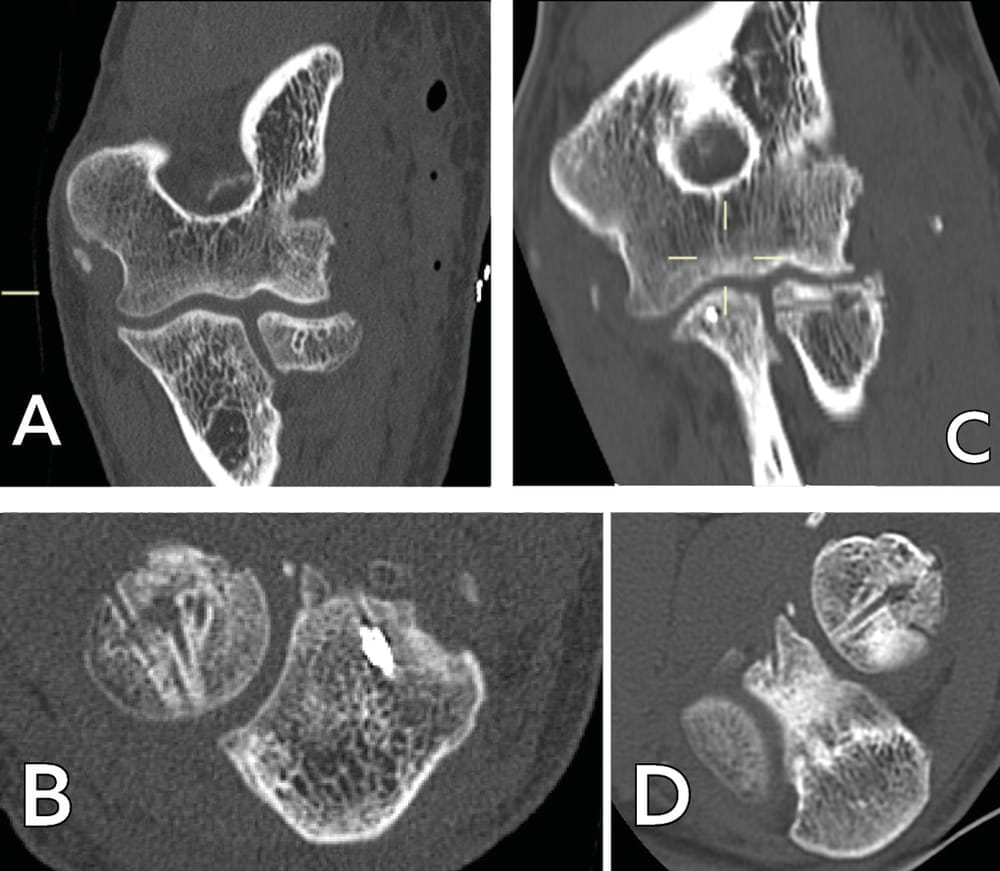

A lateral approach is used to open the radiohumeral compartment; this may be easier if there is an injury to the lateral collateral ligament, which is often part of the picture in complex joint trauma. Exposure of the radial head, the bone fragments and capitellum follows the same method whether for ORIF or replacement. Related interventions, such as coronoid process ORIF or reinsertion of the anterior capsule, are performed. A standard ORIF is carried out by reducing the fragments and temporary fixation with pins. This is followed by an assessment of bone loss: circular segment or chunk. The bone loss contour is mapped onto the lateral surface of capitellum. If the segment is circular (Figure 1), the length of the line is measured and transferred. A mini oscillating saw is using to harvest a graft with a sagittal thickness of 4–5 millimetres, depending on the extent of bone loss. The ORIF is performed using mini screws of 1.5 or 2mm diameter (Figure 2), with or without a console plate, exercising caution in the “safe zone” to avoid any proximal radio-ulnar impingement. A cancellous bone graft can also be harvested if necessary. The osteochondral graft is harvested in the sagittal plane and positioned in the axial plane, with the lateral surface of capitellum (the graft) becoming the superior surface of the radial head.

Case study 1: A 49-year-old right-handed male electrician fell from a stepladder, which led to bilateral elbow fracture dislocation (Mason 4). An emergency closed reduction was performed. Subluxation of the left elbow persisted, with damage to the ulnar nerve. After CT investigation (Figure 3), ORIF appeared to be possible, a more viable option since a prosthetic radial head would not be available for at least 5 days.